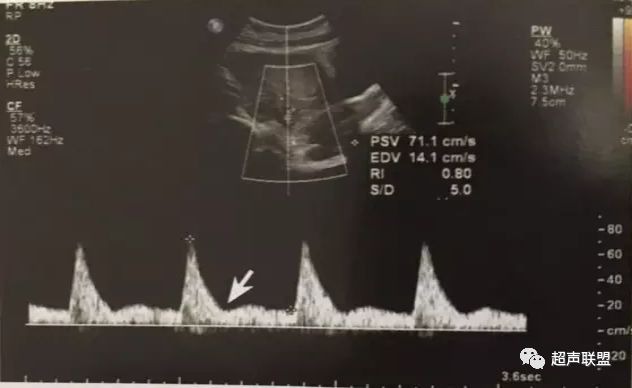

图3 正常大脑中动脉血流频谱